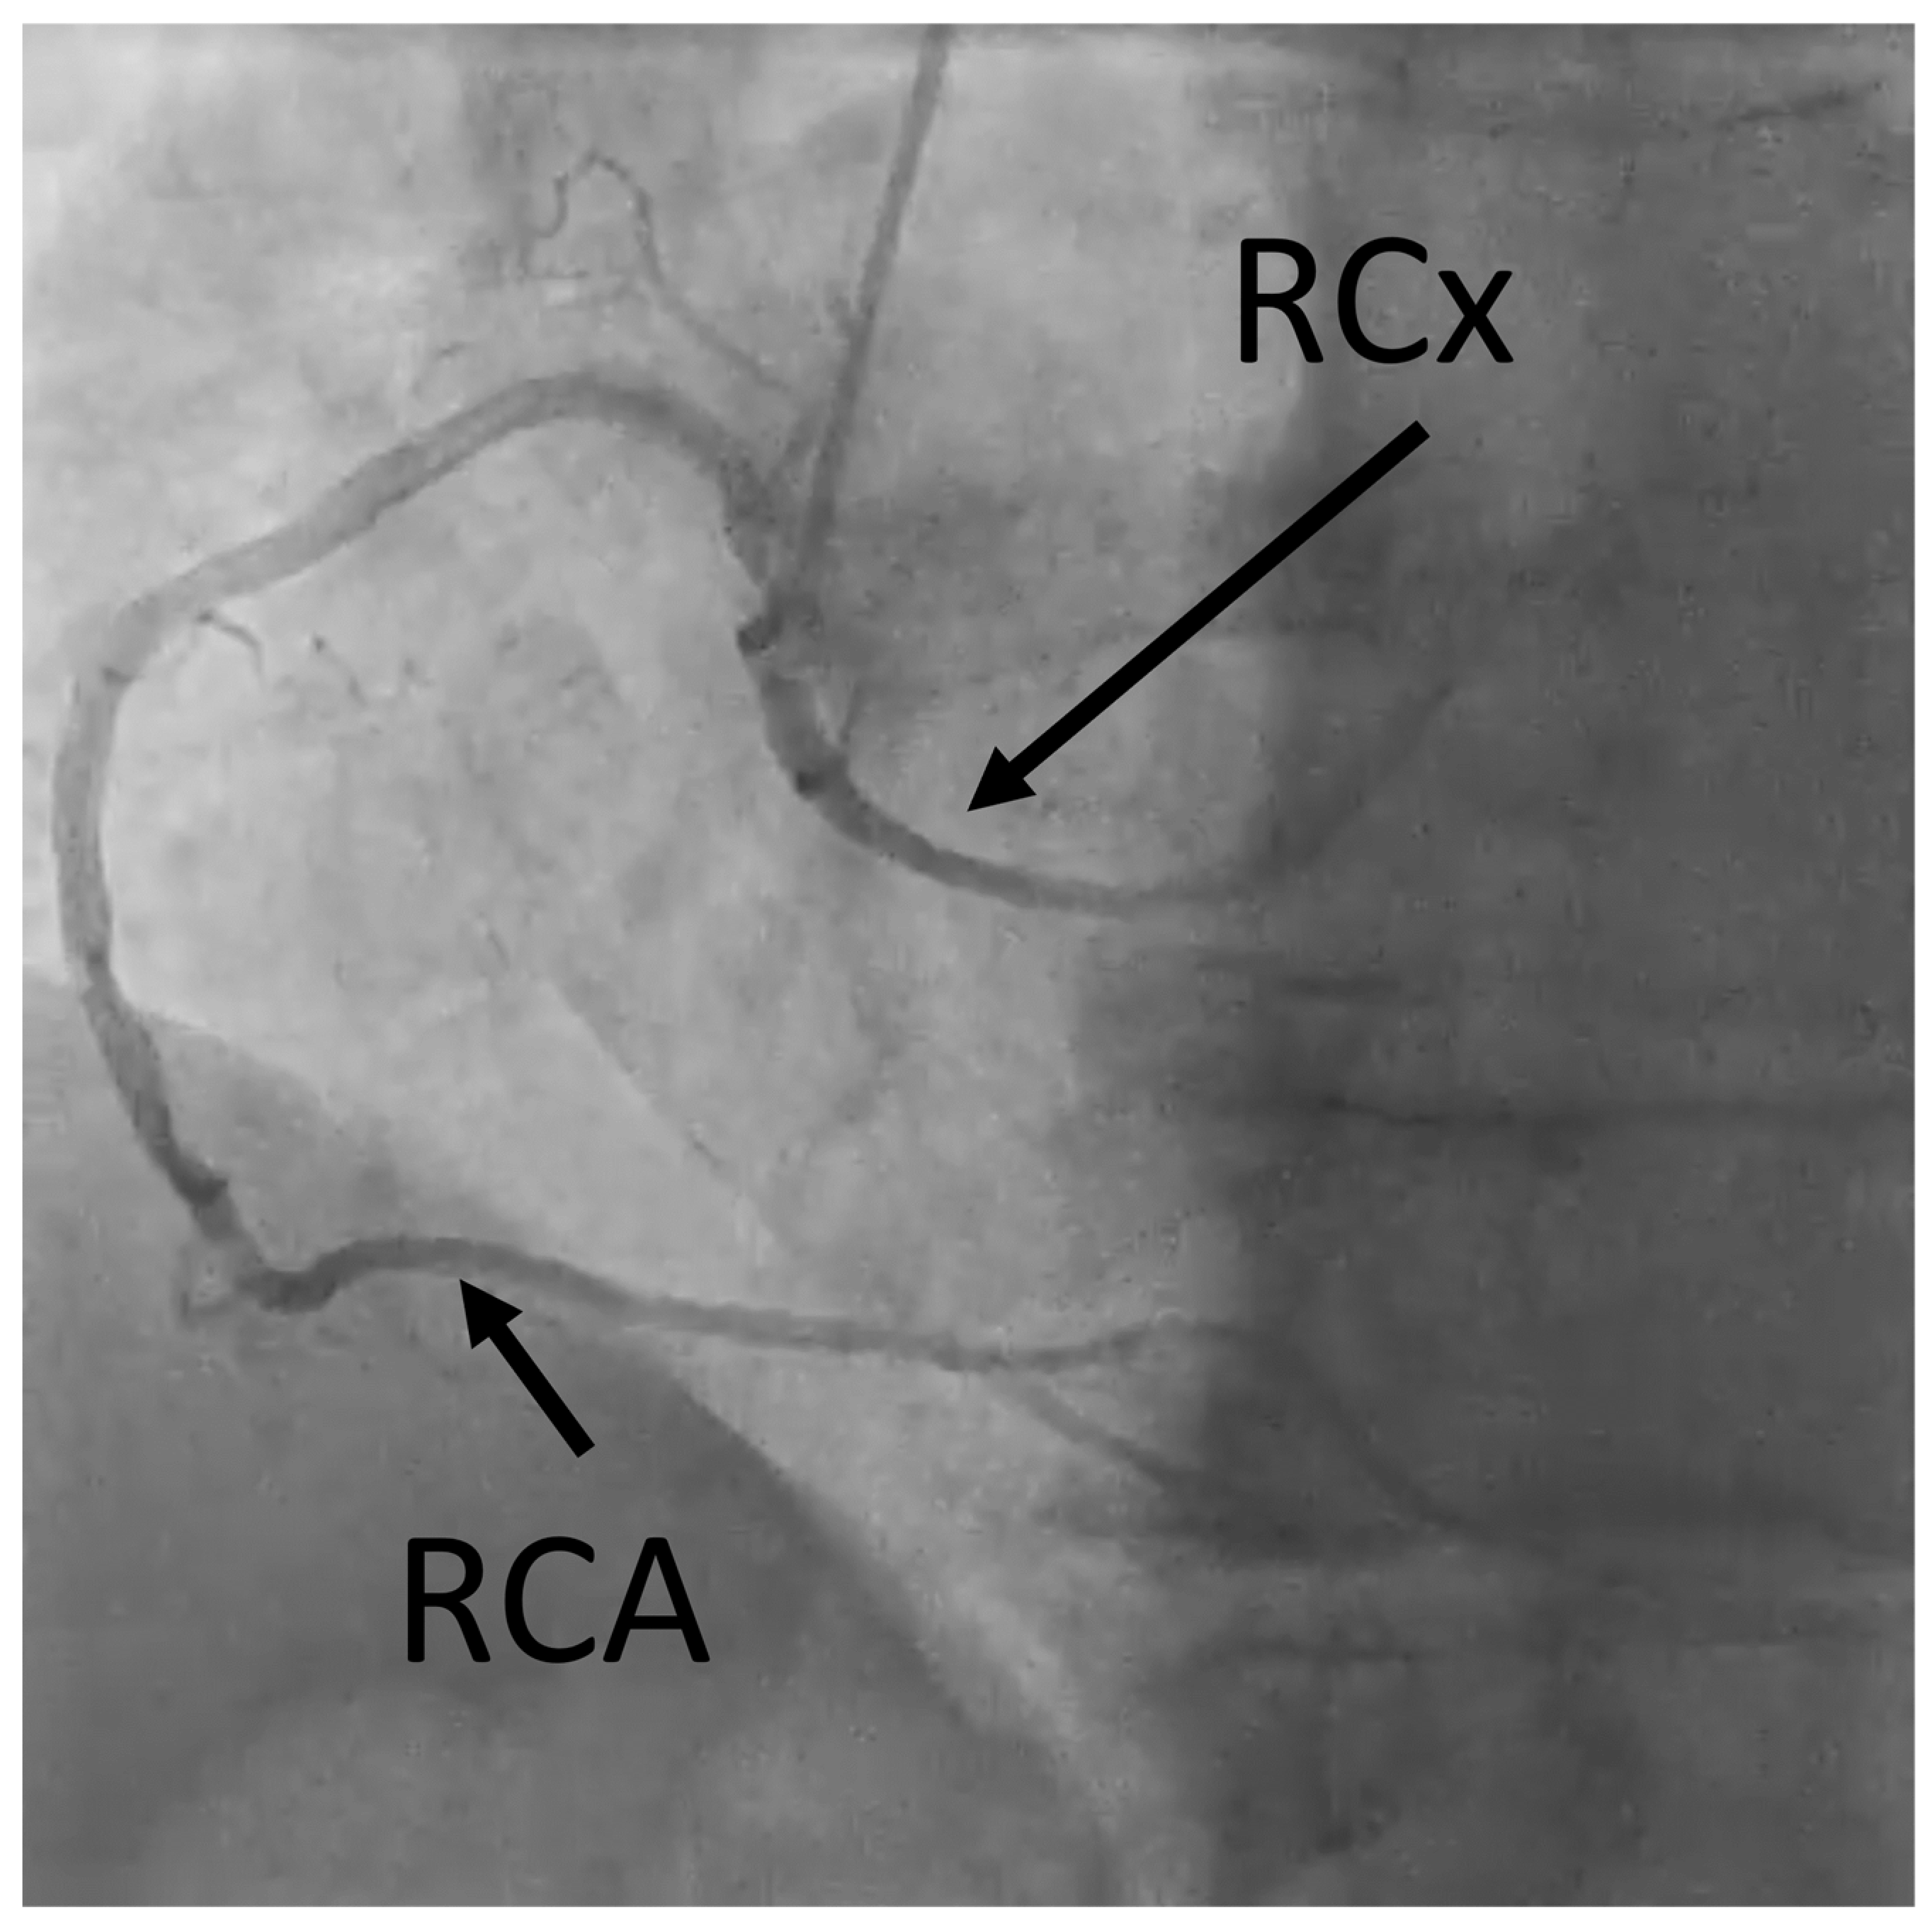

3.2. Radiologic